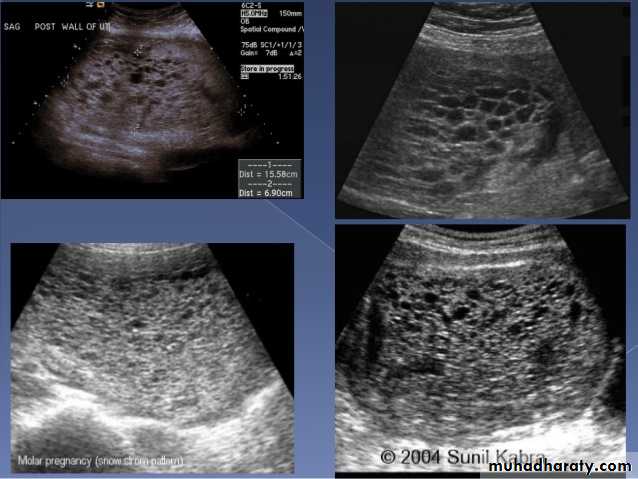

Molar pregnancy

Gestational trophoblastic disease (GTD) results from abnormal proliferation of trophoblastic tissue, and encompasses a wide spectrum of diseases, including:hydatidiform mole

complete mole

partial mole

invasive mole

Chorio carcinoma (gestational choriocarcinoma)

Radiographic features

Ultrasound

enlarged uterus

classic sonographic appearance is that of a solid collection of echoes with numerous small (3-10 mm) anechoic spaces (snowstorm appearance).

the molar tissue demonstrates the punch of grapes sign which represents hydropic swelling of trophoblastic villi.